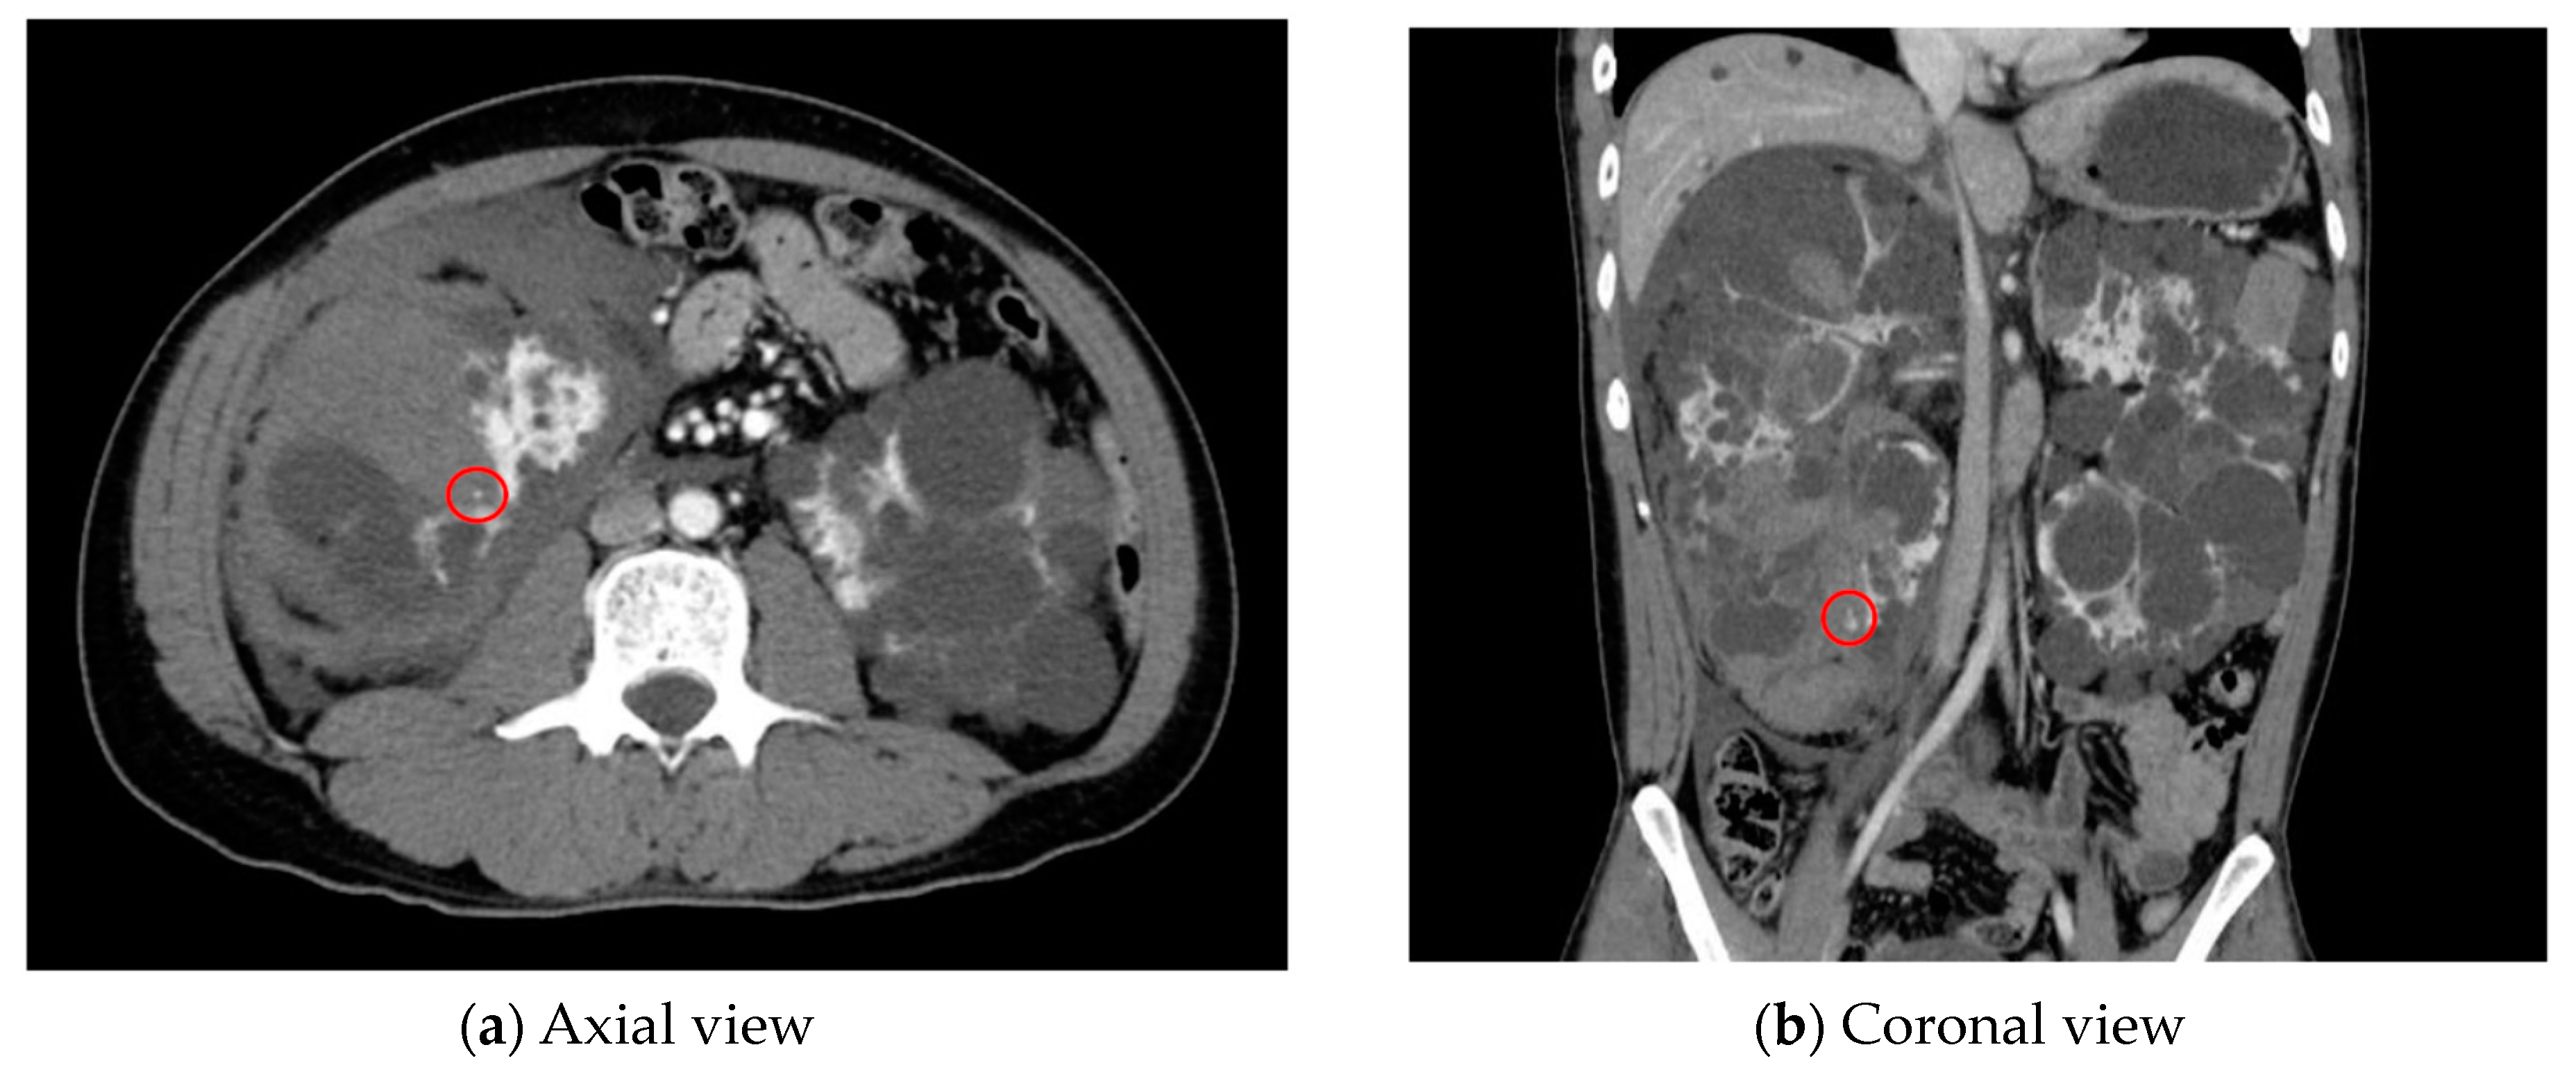

- AI for Image Analysis: AI-based image analysis algorithms can enhance the detection and diagnosis of extravasation events in imaging studies, such as ultrasound, MRI, and CT. These algorithms can automatically identify subtle signs of extravasation, assist healthcare providers in interpreting the imaging findings, and facilitate a timely intervention. This suggestion is subsequently extended as a separate discussion.